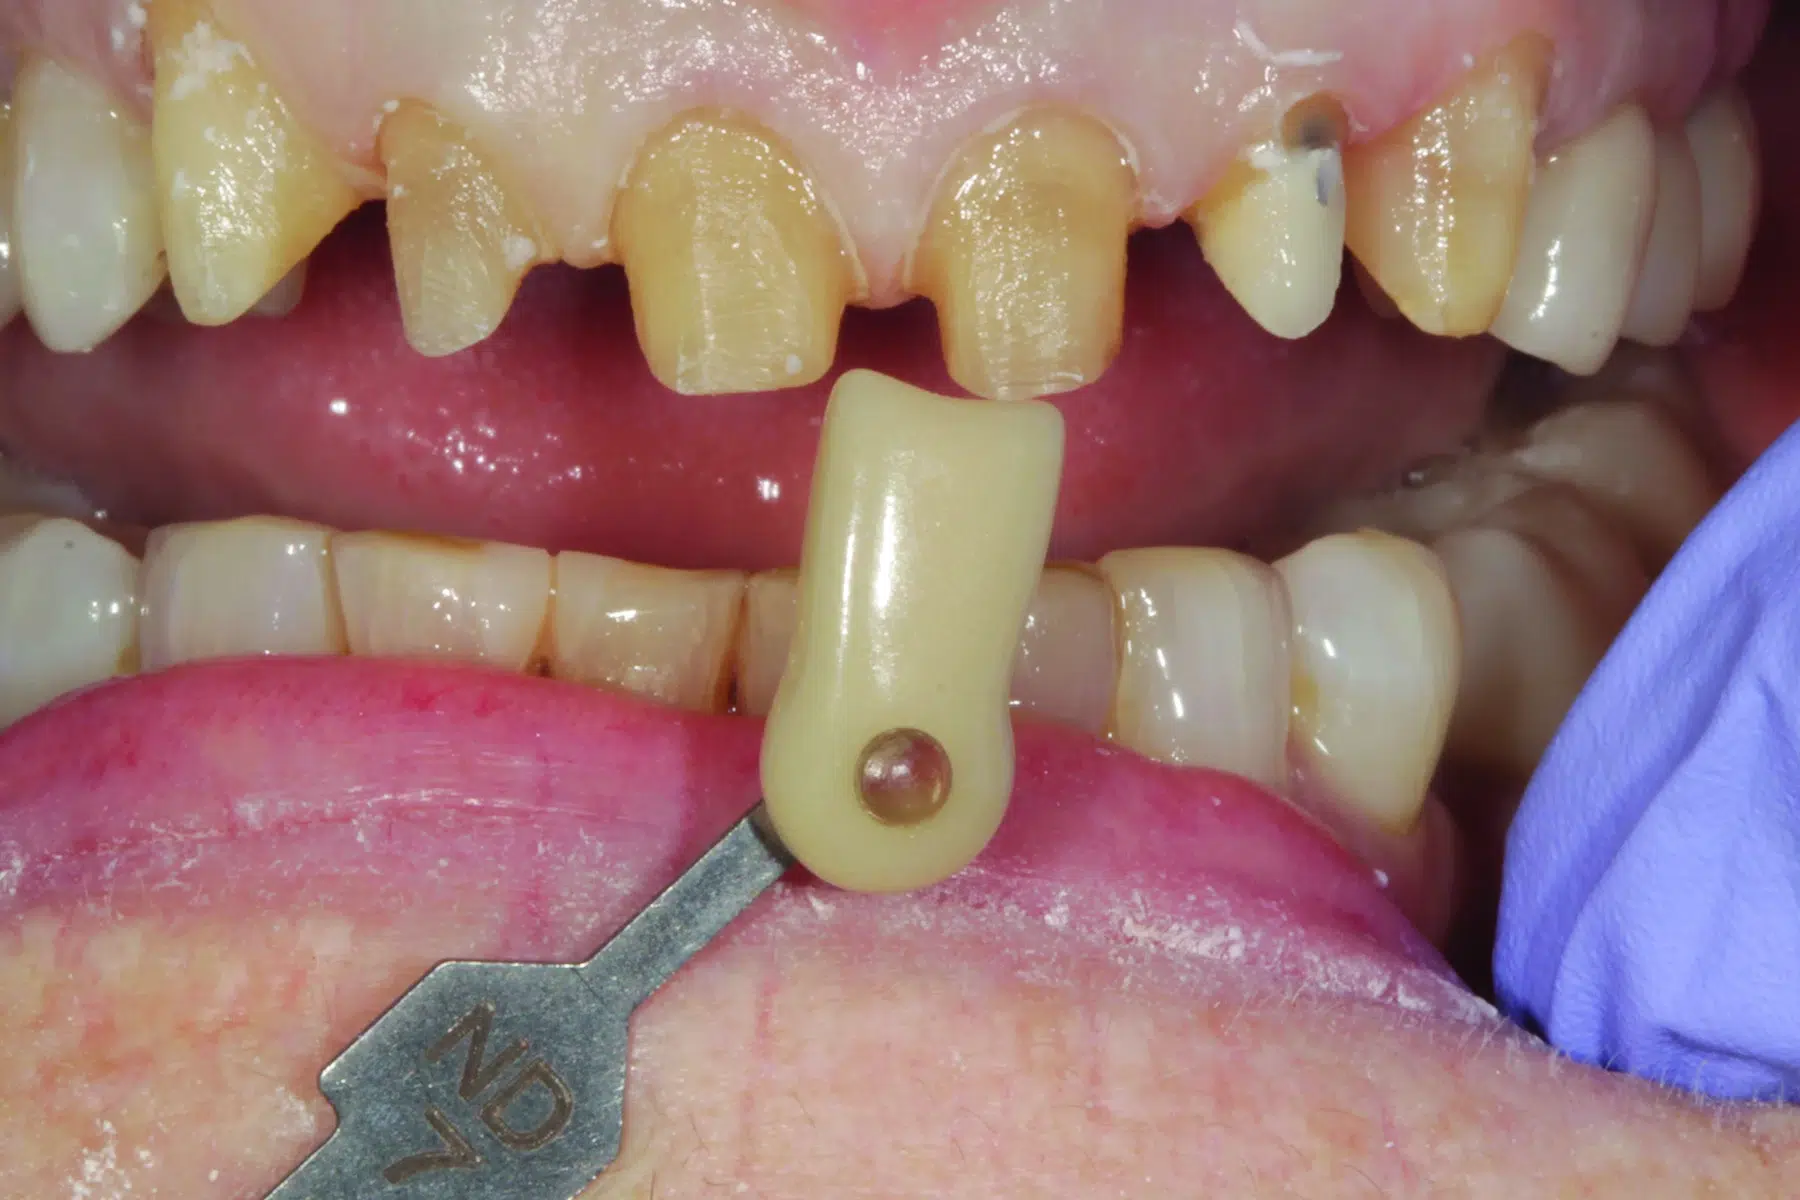

En, sedan många år tillbaka, kvinnlig patient, nu i tidig 70-års ålder kom till praktiken, missnöjd med oestetisk färg och form på tand nr 22 (bild 1). Många år tidigare hade tanden blivit endodontiskt behandlad. En metallpelare hade cementerats för att bygga upp och stärka tanden inför en metallkeramisk krona (bild 2), som utformades så att den skulle maskera stiftets färg. Vid undersökningen påtalade tandläkaren att den mesiala ytan på tand 11 hade flisats av. Han föreslog att den tanden också skulle behandlas, tillsammans med missfärgningarna på tänderna 12 och 21 (bild 3). Den rekommenderade behandlingsplanen innebar att förse tänderna 11-13 och 21-23 med helkeramiska restaurationer. Efter att patienten hade gått med på behandlingsförslaget och innan behandlingen satte i gång, tog tandläkaren en serie extra- och intraorala bilder för kommunikationen med det tandtekniska laboratoriet. Vid behandlingstillfället bedövades patienten och kronan på 22 togs bort och tänderna 11-13 och 21- 23 preparerades för helanatomiska kronor. För att kommunicera pelarfärgen till laboratoriet, fotograferades preparationerna med ett färgprov (IPS Natural Die Material Shade Guide ND7, Ivoclar) (bild 4) och skannades digitalt (Trios 4, 3Shape). Temporära restaurationer framställdes med en prefabricerad skena som hade tillverkats efter starttillfällets diagnostiska design (PerfecTemp II, DenMat).

- (4.) De preparerade tänderna fotograferades tillsammans med ett färgprov för att kommunicera pelarfärgen med laboratoriet.